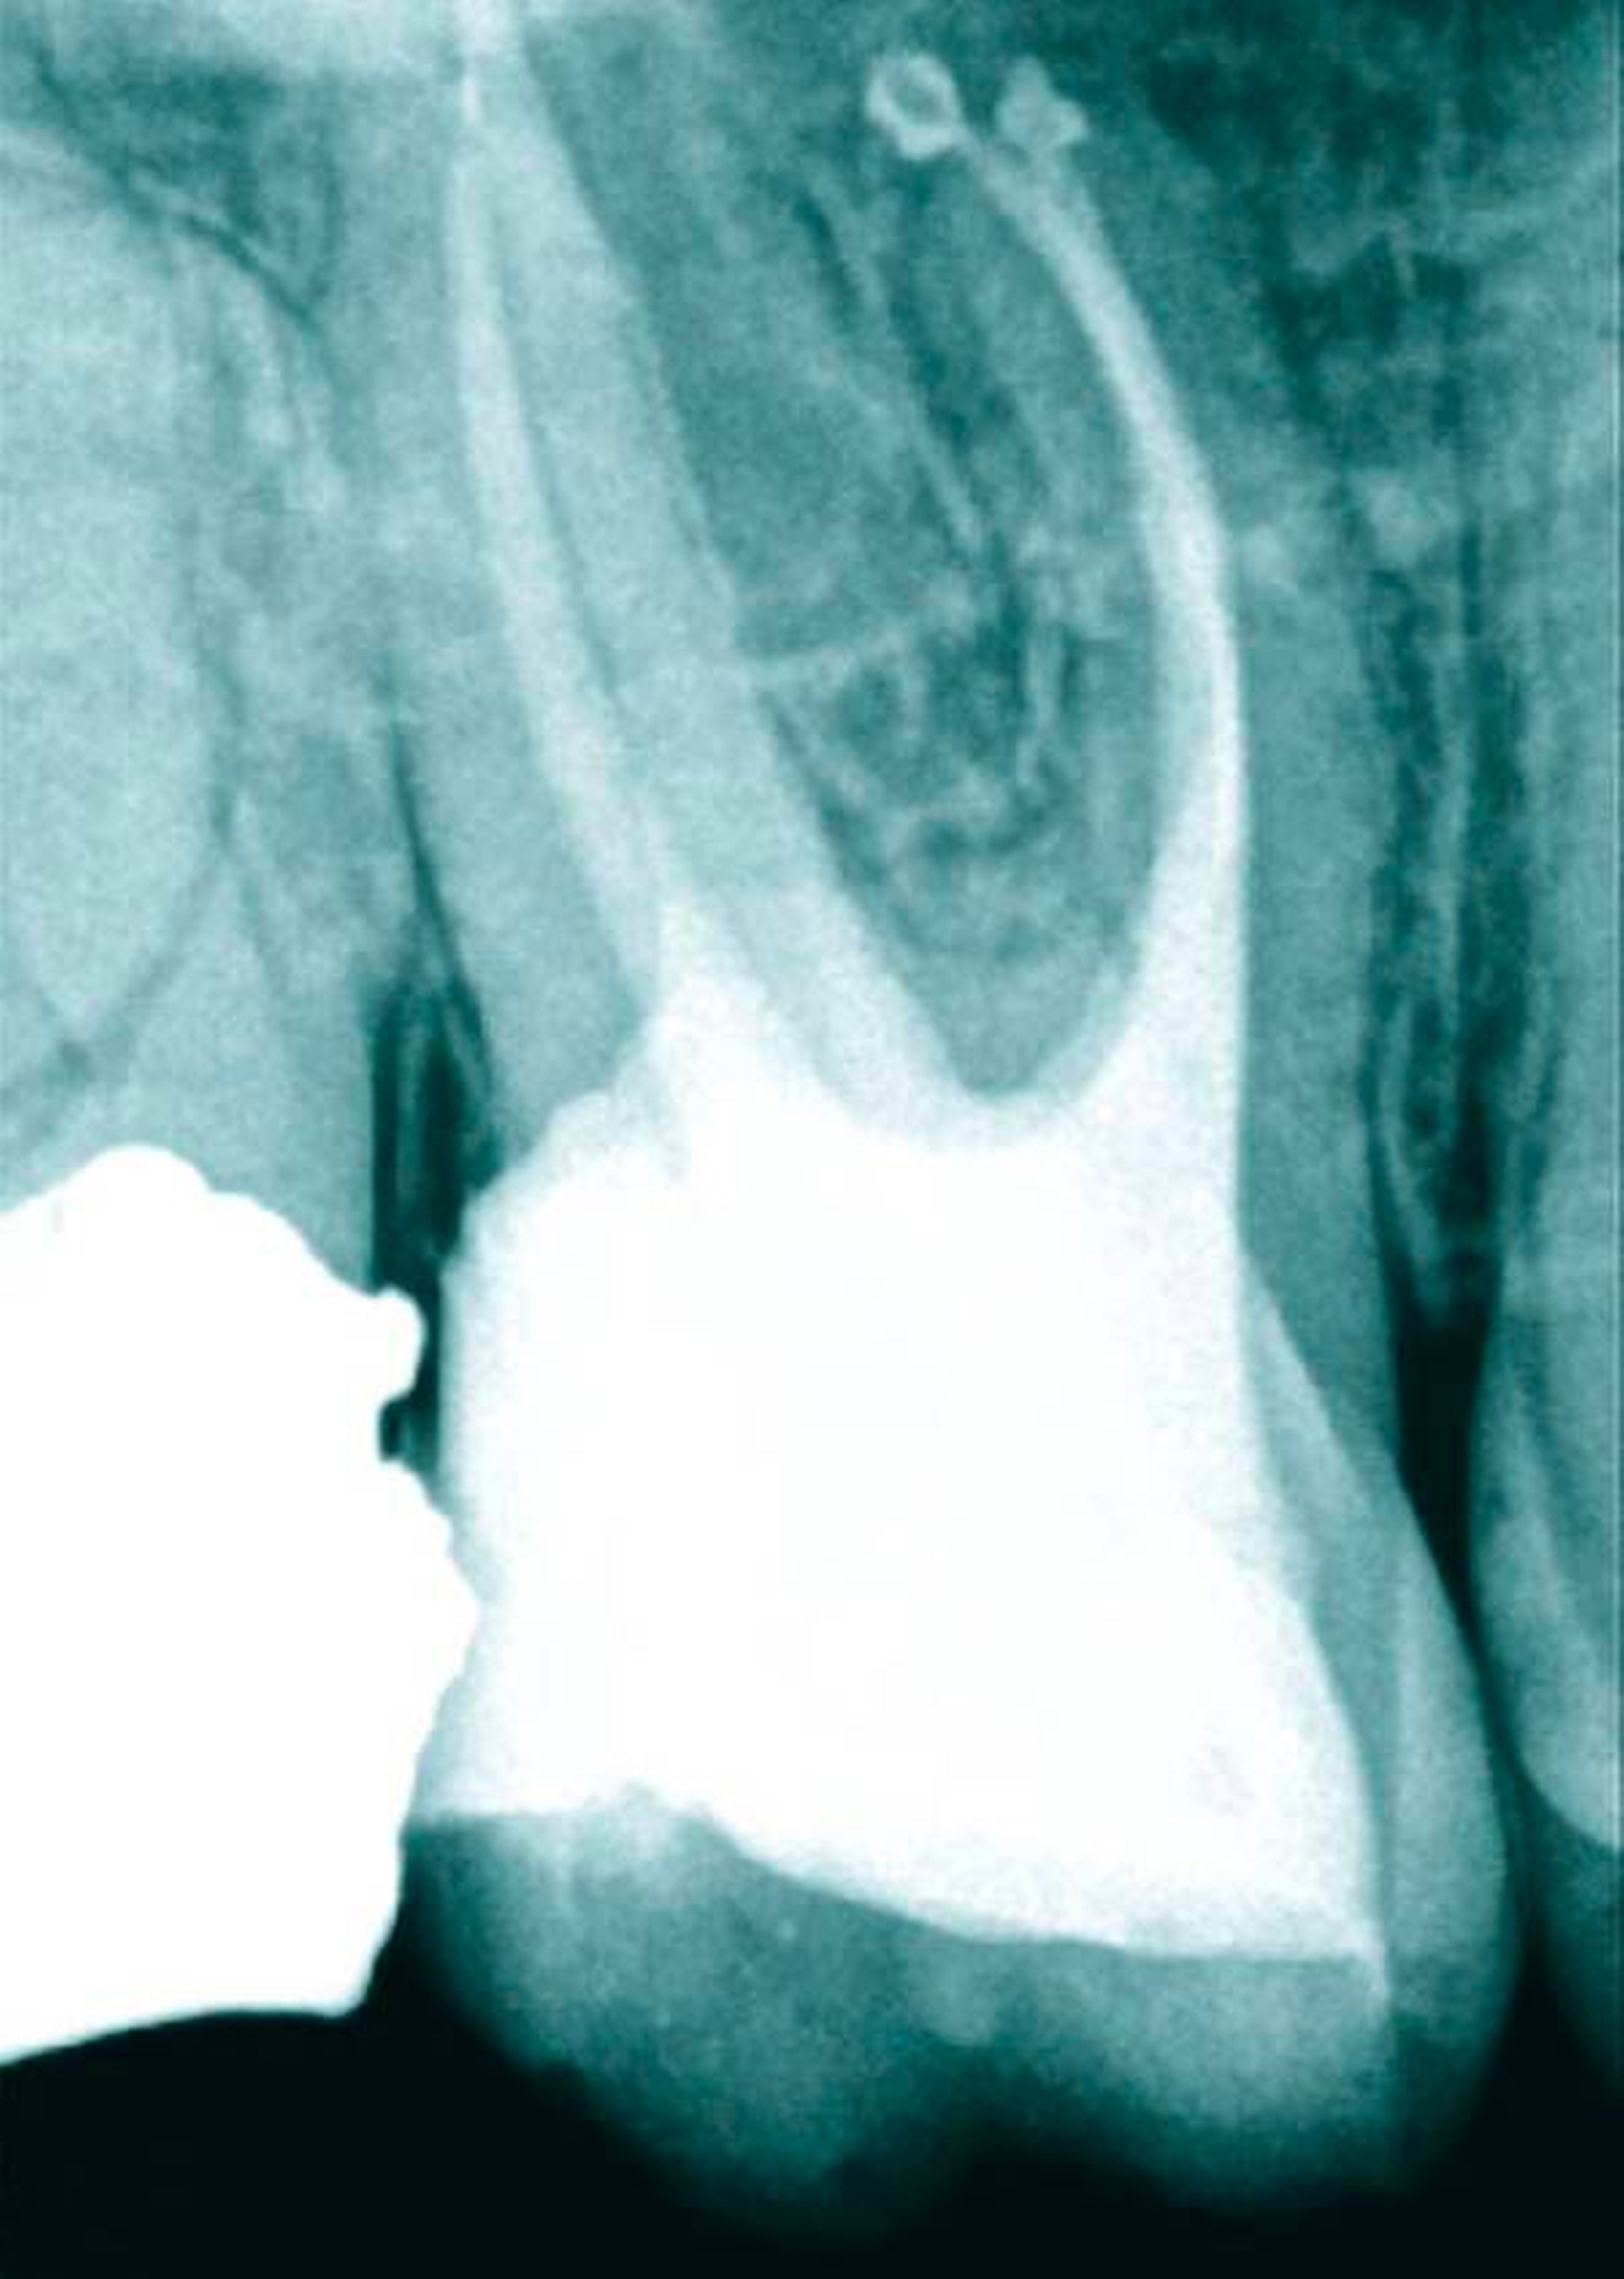

Die aktuelle Forschung kann auf hochauflösende Verfahren zur Ermittlung von Wurzelkanalsystemen zurückgreifen. Die destruktiven Verfahren werden dabei mehr und mehr von nondestruktiven Verfahren (MikroCT, NanoCT, MRT) abgelöst [Parkinson & Sasov, 2008; Paqué et al., 2010] (Abbildungen 2 und 3). Mit der dentalen Digitalen Volumentomografie (DVT) gelingt es erstmals am Patienten, die tatsächliche Form und den Verlauf von Wurzeln in Beziehung zu pathologischen Prozessen darzustellen (Abbildung 4) und aus der Form der Wurzel Rückschlüsse auf die Anzahl und die genaue Lage der Wurzelkanäle zu ziehen [DVT-Leitlinie DGZMK S2, 2009; Patel, 2009; Michetti et al., 2010].

Die Auseinandersetzung mit der bisweilen sehr komplexen Anatomie des Wurzelkanalsystems soll den Zahnarzt keineswegs entmutigen – im Gegenteil: Mit mehr Wissen und Erfahrung können auch schwierige Fälle erfolgreicher therapiert werden. Die dreidimensionale Darstellung des Wurzelkanalsystems mithilfe der Computertomografie führt zu einem besseren Verständnis einer komplexen anatomischen Struktur und ermöglicht die Entwicklung neuer minimalinvasiver Behandlungstechniken. Die Indikation zur Anfertigung einer dentalen DVT-Aufnahme ist jeweils individuell zu bestimmen und orientiert sich am Nutzen für den Patienten [Schulze et al., 2013]. Präoperative DVT-Aufnahmen erhöhen die diagnostische Sicherheit und beeinflussen signifikant die Therapieentscheidung [Mota de Almeida et al., 2014]. Das Ermitteln der tatsächlichen Wurzelform und möglicher tiefer Aufzweigungen von Wurzelkanälen kann dann den Erfolg der Therapie positiv beeinflussen, wenn gleichzeitig die Informationen aus der dentalen DVT mit einer optischen Vergrößerung (Lupenbrille 6x oder Dentalmikroskop) am Patienten wieder aufgefunden werden können.